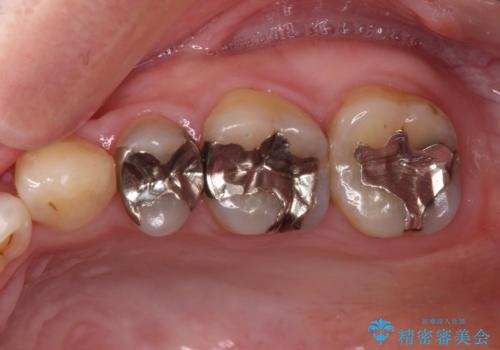

- 他院で抜歯矯正を終えた後、銀色の目立つ奥歯を白くしたいとのことで来院された患者様です。

既にセラミッククラウンが装着されている歯もありますが、不自然な色合いや黒い縁も気になるので、一斉に補綴治療をして統一感を持たせることとしました。